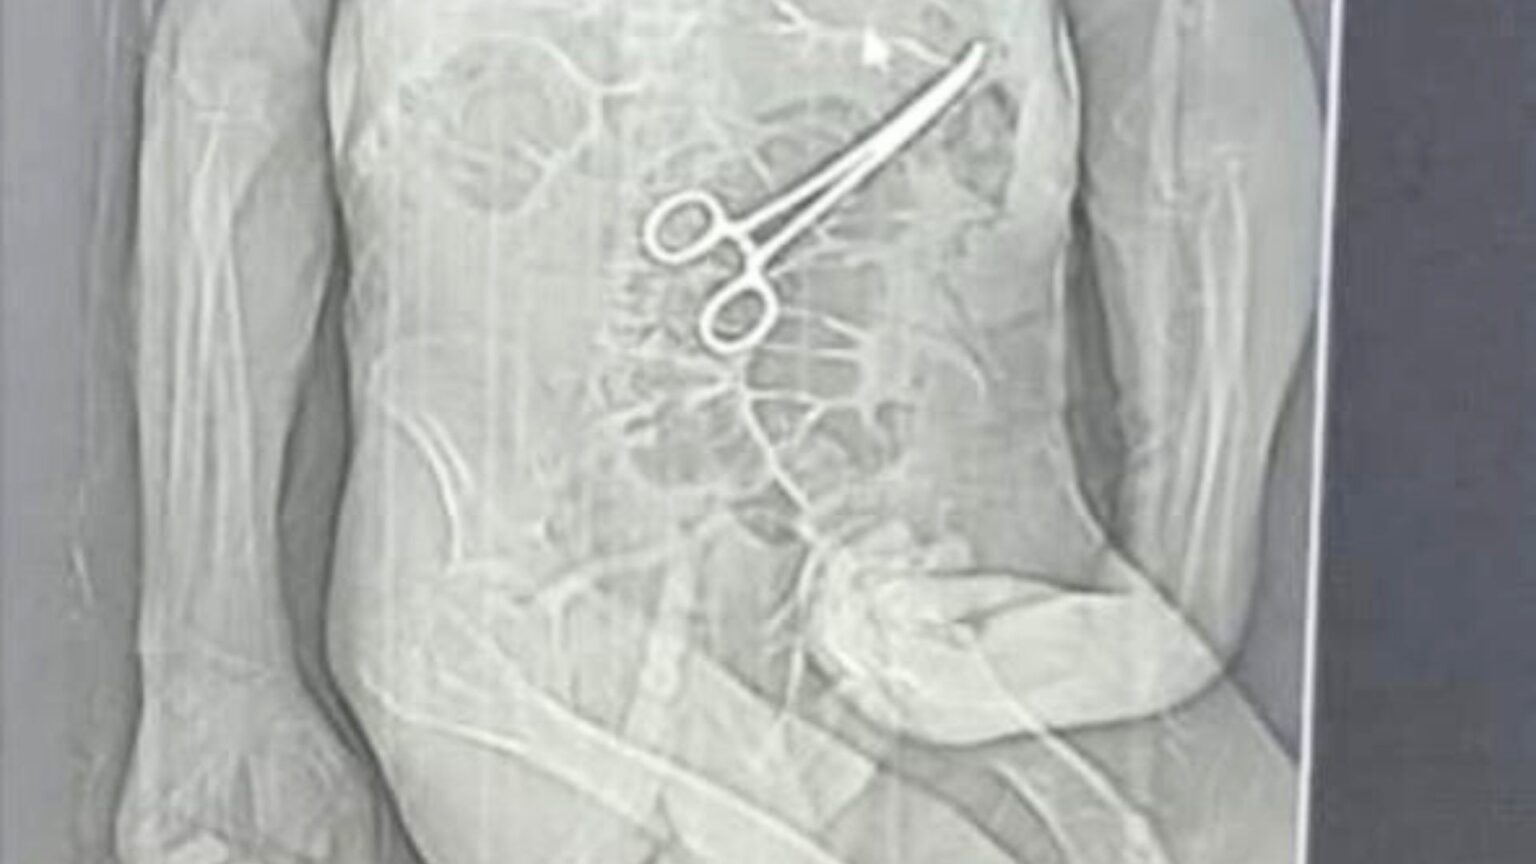

Na véspera do Natal, um idoso de 68 anos faleceu em um hospital de Minas Gerais, um dia antes de completar 69 anos. O caso, que chocou a comunidade local, ocorreu após duas cirurgias em que, segundo a família, uma pinça foi esquecida dentro do corpo do paciente. A Secretaria Municipal de Saúde de João Pinheiro confirmou, em nota, a presença do corpo estranho e ressaltou que a vítima, Manoel Cardoso de Brito, já apresentava várias comorbidades, o que complicou sua condição de saúde.

Após a segunda intervenção cirúrgica, a equipe médica comunicou que retirou pus e um dreno da cavidade interna do paciente. Embora Manoel tenha sido levado de volta para a UTI, ele não resistiu e faleceu 13 dias após sua internação. Segundo o advogado da família, Iuri Evangelista Furtado, a busca por medidas legais se intensificou após a divulgação de um exame de tomografia que evidenciou a presença da pinça esquecida no corpo do paciente.

De acordo com a nota oficial, durante a segunda cirurgia, não foram encontradas perfurações intestinais e as suturas do primeiro procedimento estavam intactas. A família foi informada sobre a retirada do corpo estranho apenas após a cirurgia, o que gerou ainda mais indignação entre os parentes e a comunidade.